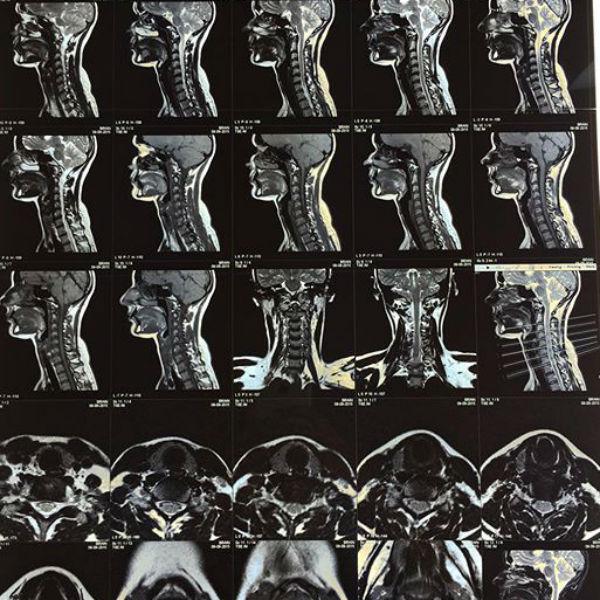

«Здорова! Не считая сильного растяжения. Спасибо Всем за переживания и слова поддержки, весь вечер обрывался телефон. 30 лет жила и никогда не видела себя изнутри. Вот теперь познакомилась», - опубликовала запись и снимок МРТ Кожевникова.